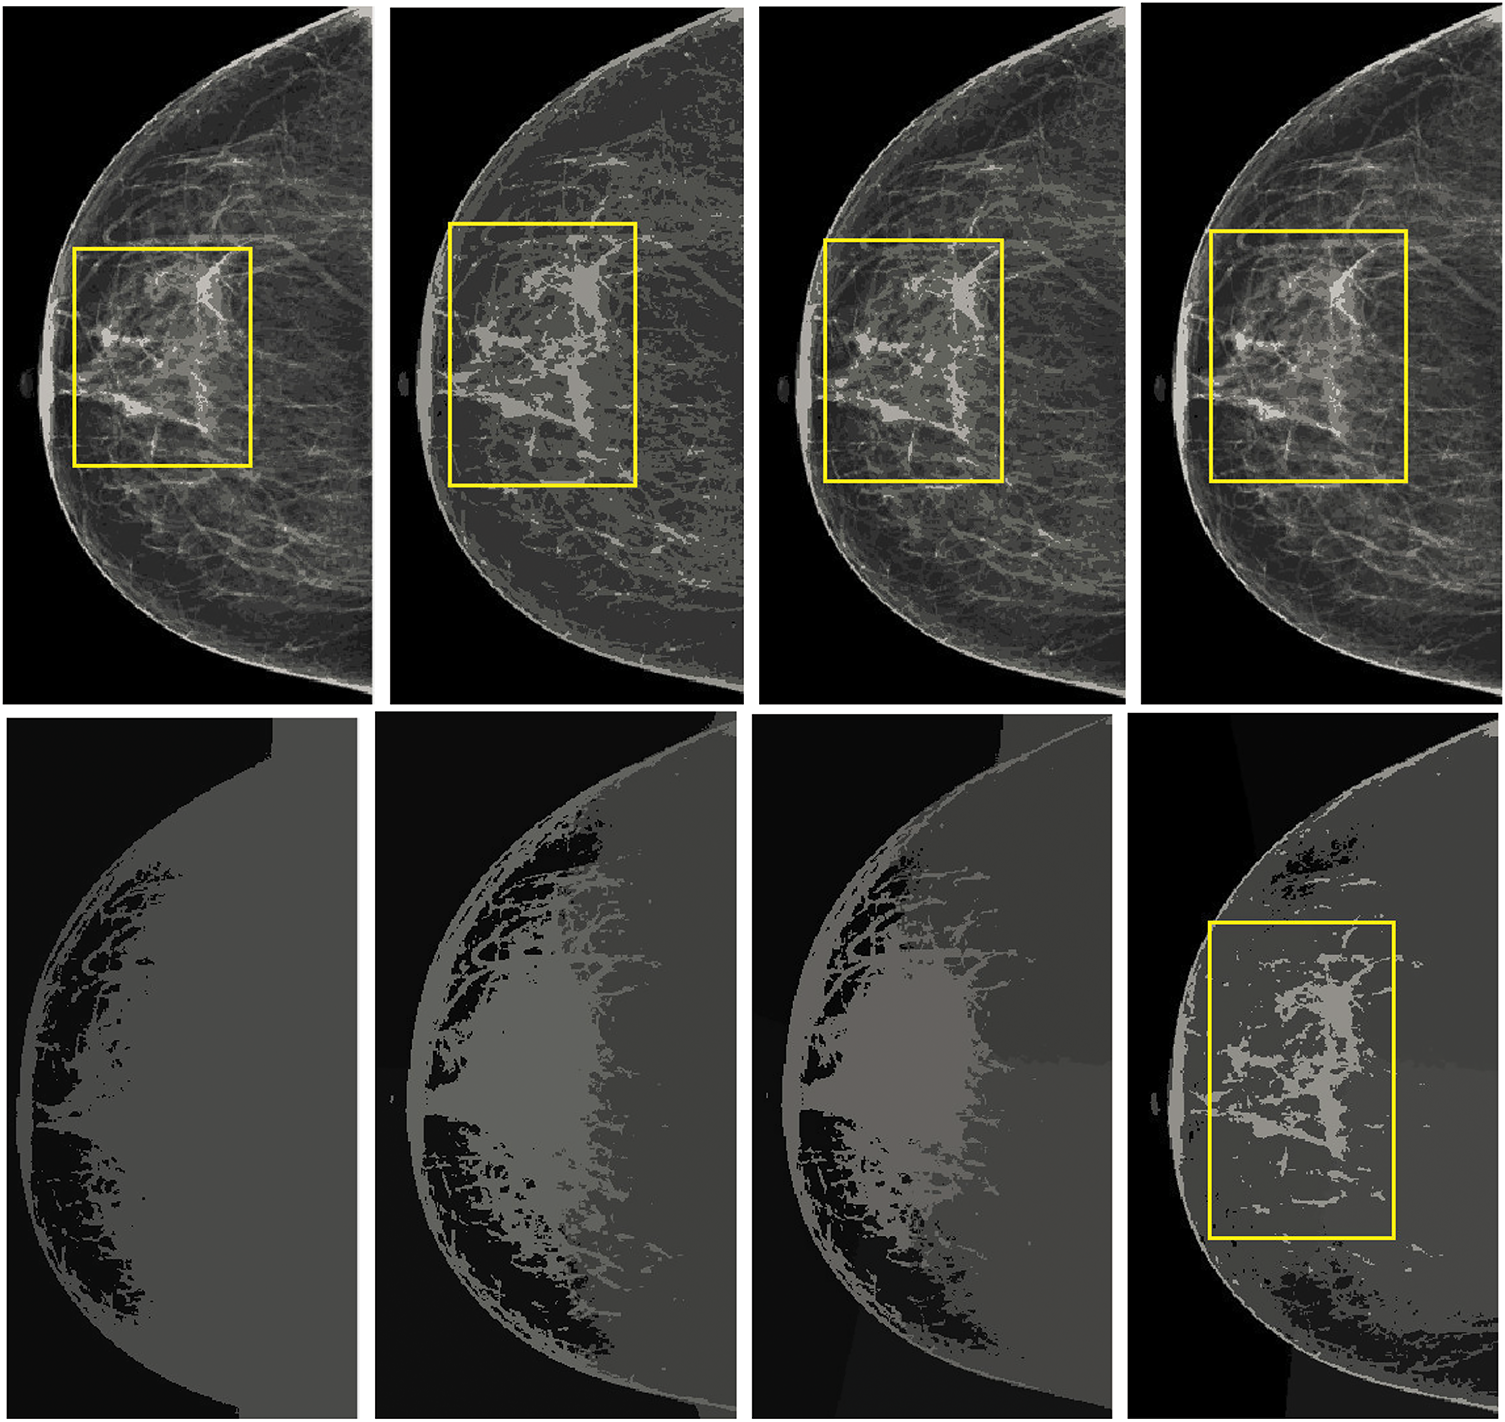

In contrast, K-means clustering, especially when applied with spatial parameters ranging from 4 to 9, exhibited superior performance by delivering cleaner segmentations with reduced noise and more detailed visualization of abnormal regions. Mean shift and its spatially-aware variations, though theoretically applicable, failed to achieve comparable results due to significant noise and low segmentation accuracy. The segmentation outputs of these techniques are illustrated in Fig. 6, where it is evident that normalized cuts and mean shift approaches were ineffective in properly segmenting mammogram scans. Conversely, the K-means method facilitated highly accurate insights into the irregular areas, enabling an improved examination of the image repositories.

Figure 6: Visualization of the mammographic image enhancement and segmentation pipeline. (a) Raw mammogram image, (b) Region of interest isolated after preprocessing, (c) Breast region extracted with pectoral muscle removed, (d) Segmented abnormal area using optimized K-means clustering, and (e) Final result showing enhanced lesion boundaries. This figure illustrates the step-by-step effectiveness of the proposed framework in refining image quality and accurately identifying suspicious regions

Overall accuracy remained above 92% across all BI-RADS categories, reflecting the method’s consistent performance across normal, benign, and malignant cases. The highest accuracy was recorded for BI-RADS 1 cases (97.36%), reaffirming the model’s precision in classifying normal tissues with minimal errors. A slight reduction in accuracy for BI-RADS 4 and 5 (92.93% and 92.81%) is attributed to the complexity of malignant cases, where distinguishing between benign and malignant features is inherently more challenging. However, the consistently high accuracy values across all categories validate the reliability of the proposed method in handling diverse mammographic conditions. The visual comparisons, as shown in Fig. 8, emphasize the superior performance of K-means in retaining crucial image details and providing better segmentation outcomes.

Figure 8: Comparison of the results from standard K-means and spatially enhanced K-means. The Ist column illustrates the outcomes with a cluster size of 2. The second column presents the results with a cluster size of 4. The third column demonstrates the outputs with a cluster size of 6, while the fourth column showcases the results with a cluster size of 8